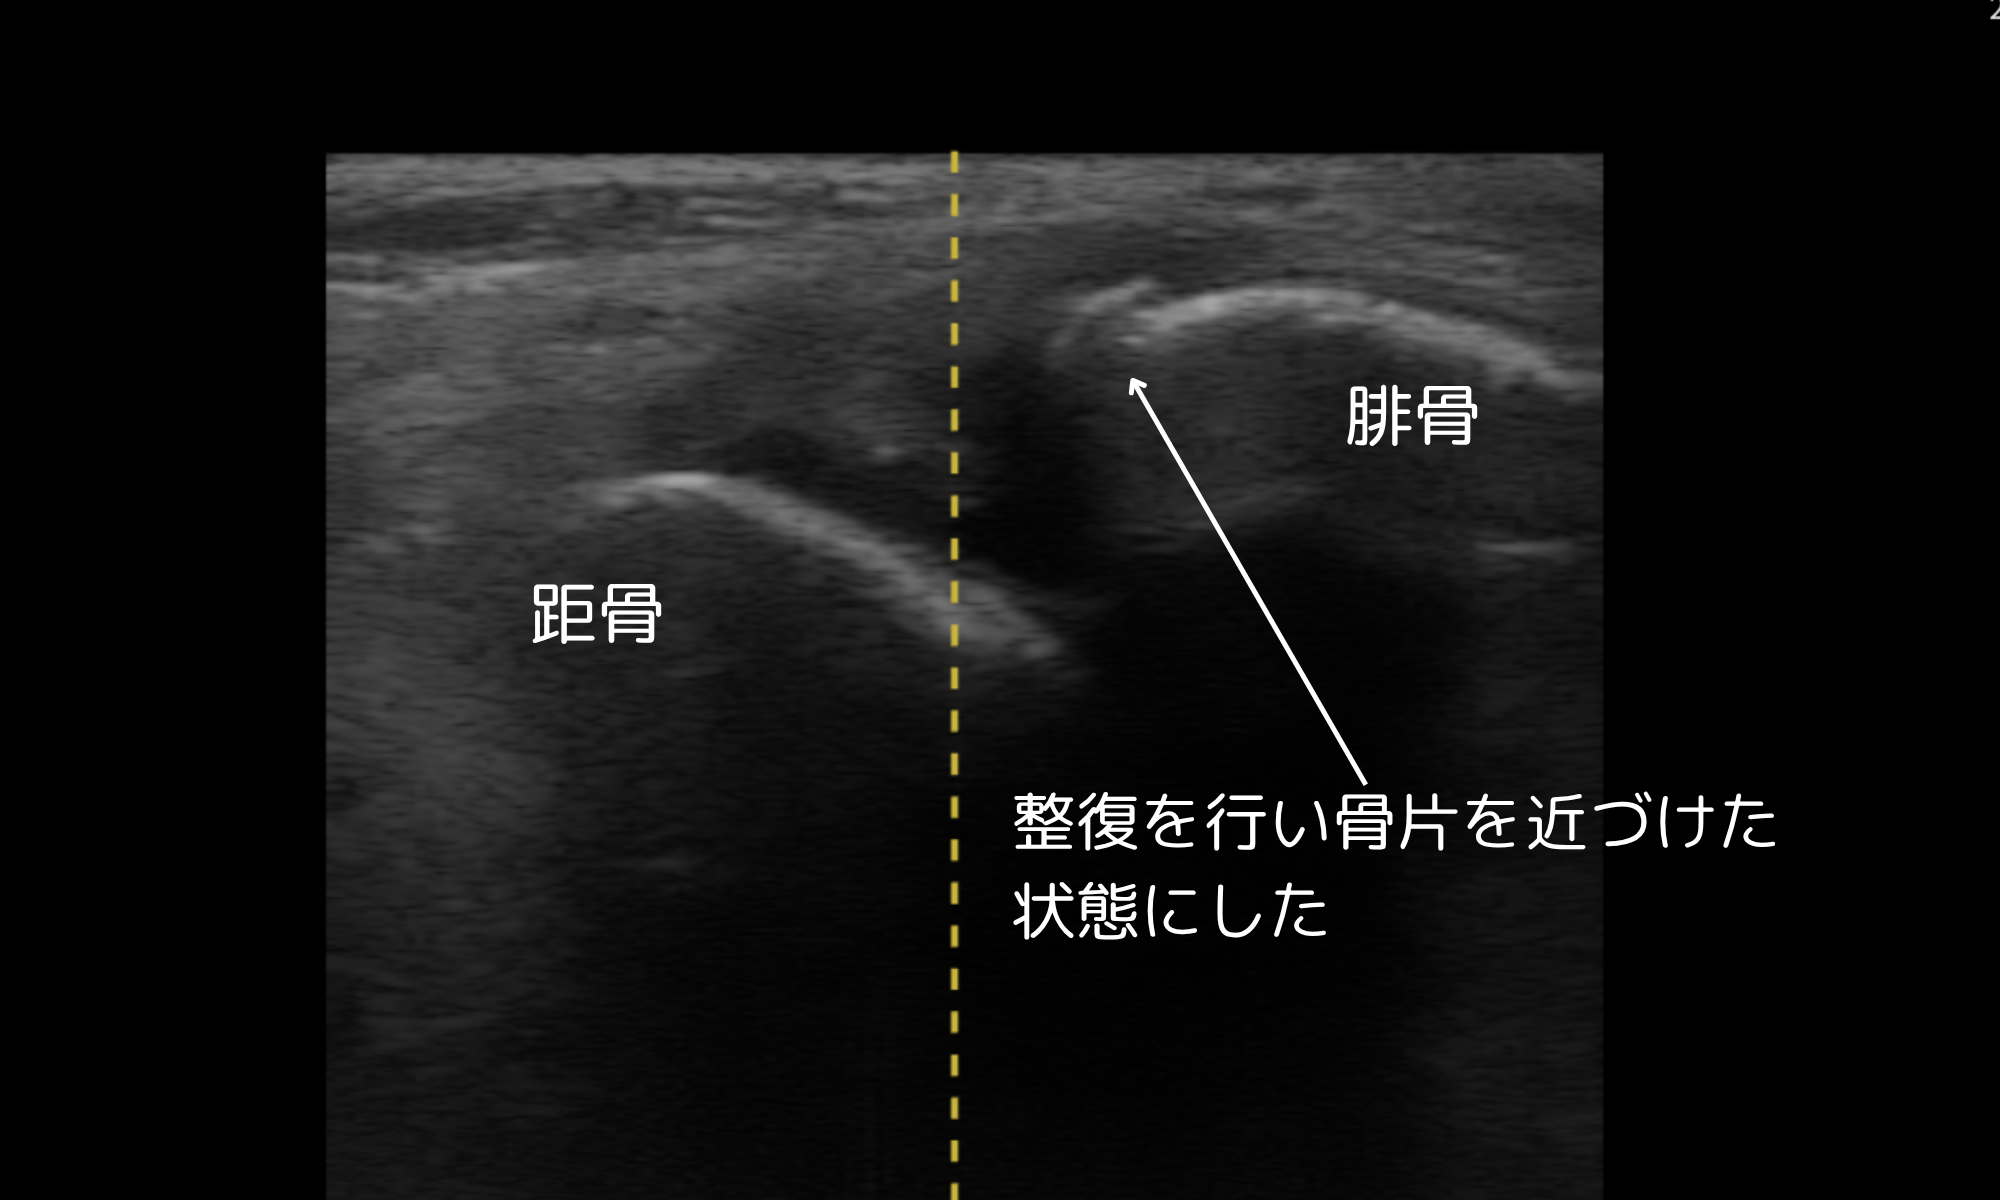

応急施療と処置

- 屈曲整復による骨片整復

- L字シーネ固定、アイシング